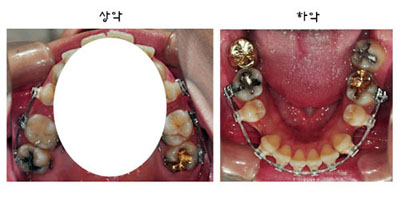

이번 월치료의 핵심은 아래 3가지에요!

1. 상악 킬본교정장치 부분탈락되어 재부착

2. 상악 좌측 어금니 와이어 부착

3. 파워체인 교체

그리고 다음으로는~

상악 좌측 어금니에 와이어를 부착했답니다.

최근 월치료동안에는 우측에만 와이어를 부착했었는데요~

이번 월치료에 상악 좌측 어금니에도 와이어를 연결해주었답니다.

마지막으로~ 하악 앞니에 파워체인 교체!

이번 월치료때 원장님께서 발치공간이 많이 닫혔다고 하시면서

돌출입교정 치료 진행이 잘 되고 있다고 말씀해주셨어요.